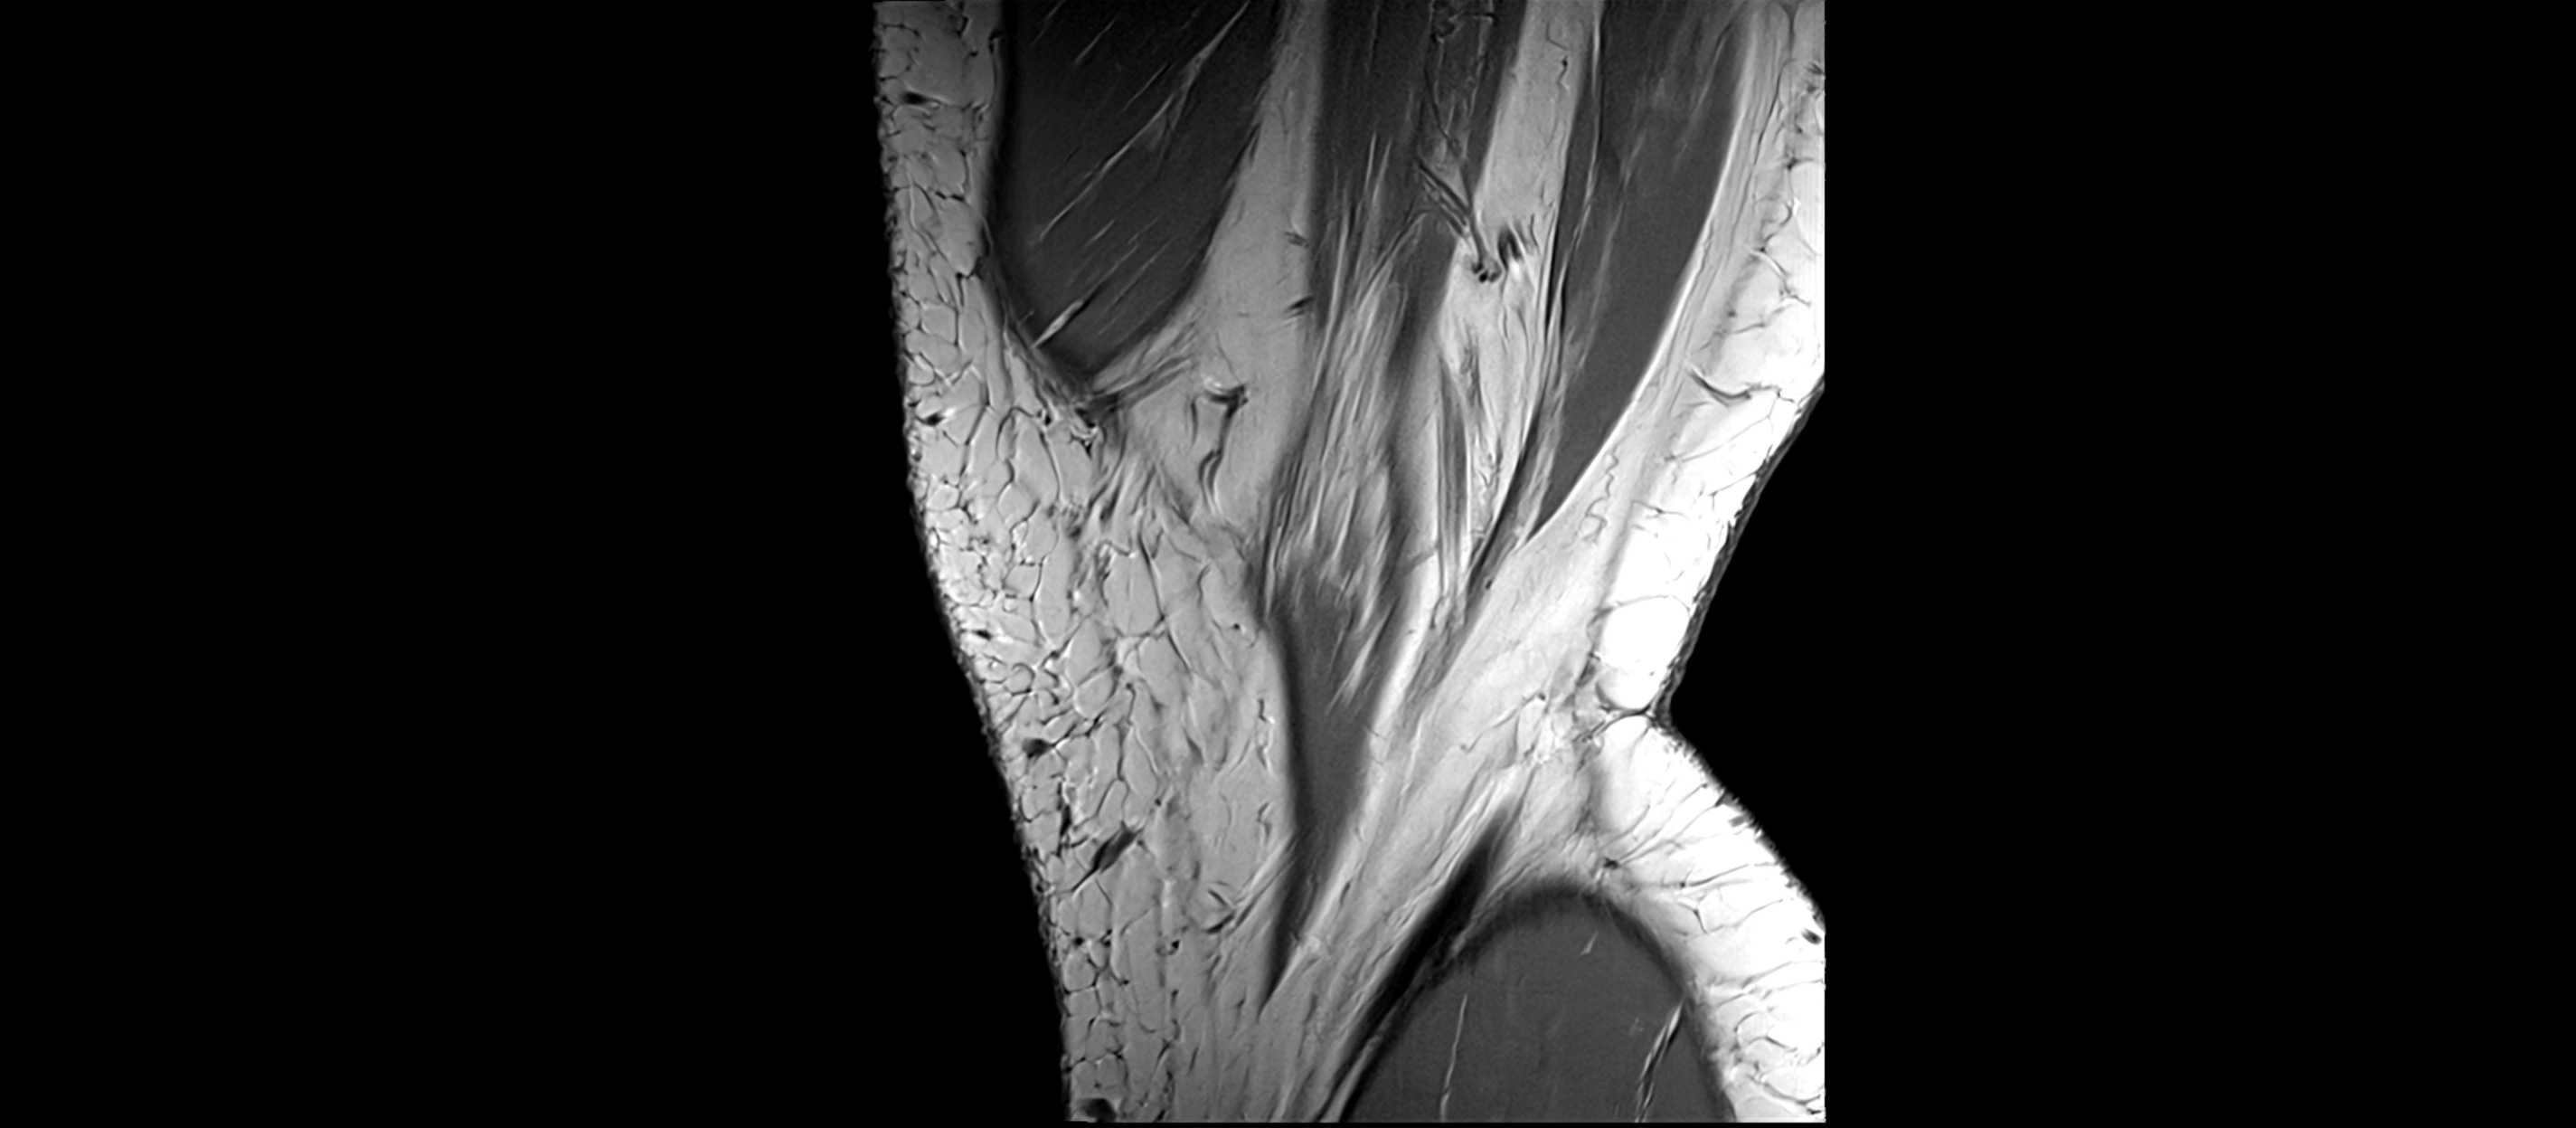

MRI images

image